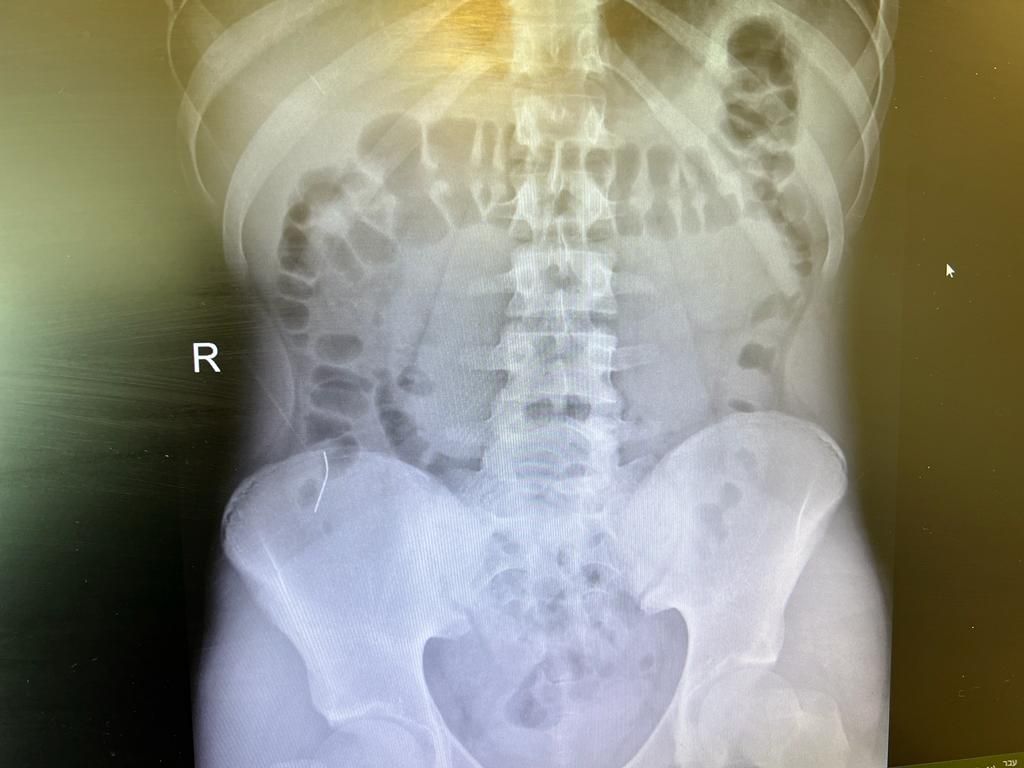

עם הגעתו לביה"ח, ביצע הנער צילום רנטגן אשר הראה כי הסיכה שבלע התקדמה לאורך מערכת העיכול והתמקמה במעבר שבין המעי הדק למעי הגס.

המקום שבו נמצאה הסיכה לא אפשר את המשך התקדמותה במערכת העיכול ובשל מיקומה היתה עלולה לנקב את איבריו של הנער ולסכן את חייו.